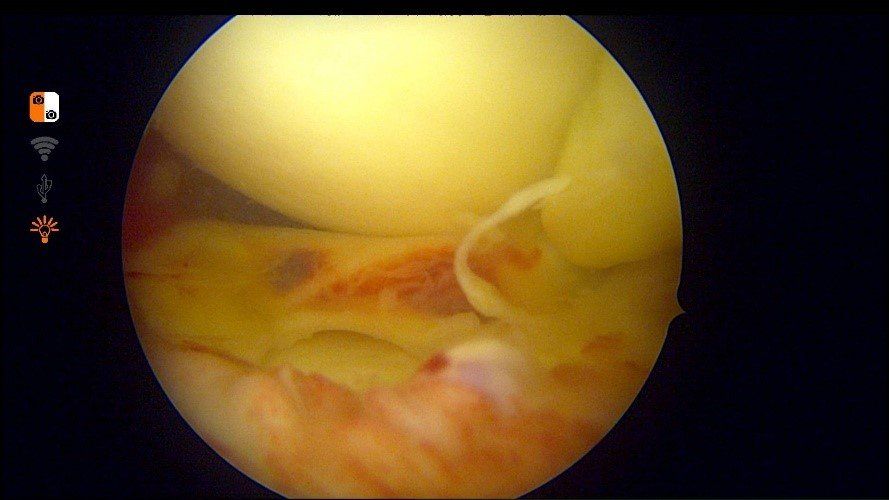

À l’extrême, le ménisque peut se déchirer en anse de seau et une languette vient se bloquer dans le genou, empêchant parfois d’étendre ou de plier le genou. C’est le « blocage méniscal ».

Il existe grossièrement 2 types de chirurgie méniscale à la Clinique du Genou. Elles sont toujours réalisées en chirurgie ambulatoire :

- Réparation méniscale sous arthroscopie : la suture méniscale est proposée chez des patients plutôt jeunes, actifs ou sportifs lorsque la fissure est située en zone favorable (rouge-rouge ou rouge blanc). La suture méniscale est un moyen de prévention de la survenue d’arthrose. En réparant le ménisque, celui-ci va reprendre son rôle d’amortisseur antichoc et de guide du genou. Toutefois, il faut soigneusement sélectionner les patients candidats, car les suites postopératoires sont plus contraignantes. D'abord, marche en appui « soulagé » à l’aide de béquilles pendant 3 semaines. La marche en plein appui sera reprise par la suite. La reprise du sport est attendue au 3e mois postopératoire.